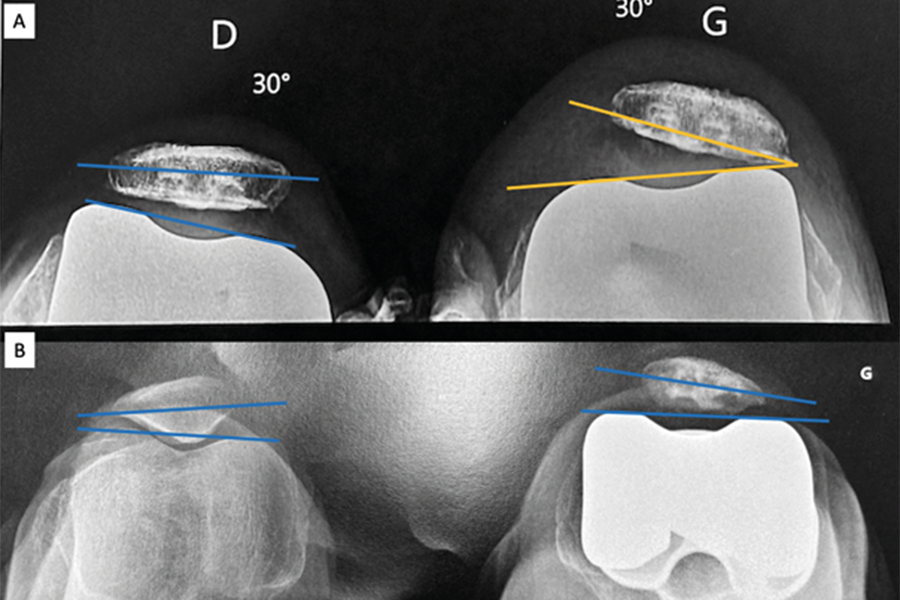

Ostéotomie fémorale distale dans la pathologie dégénérative du genou : indications, planification, techniques et complications

🖂 dejour.secretariat@lyon-ortho-clinic.com , Guillaume Demey Lyon Ortho Clinic - Clinique de la Sauvegarde, 29B avenue des Sources, 69009 Lyon, France